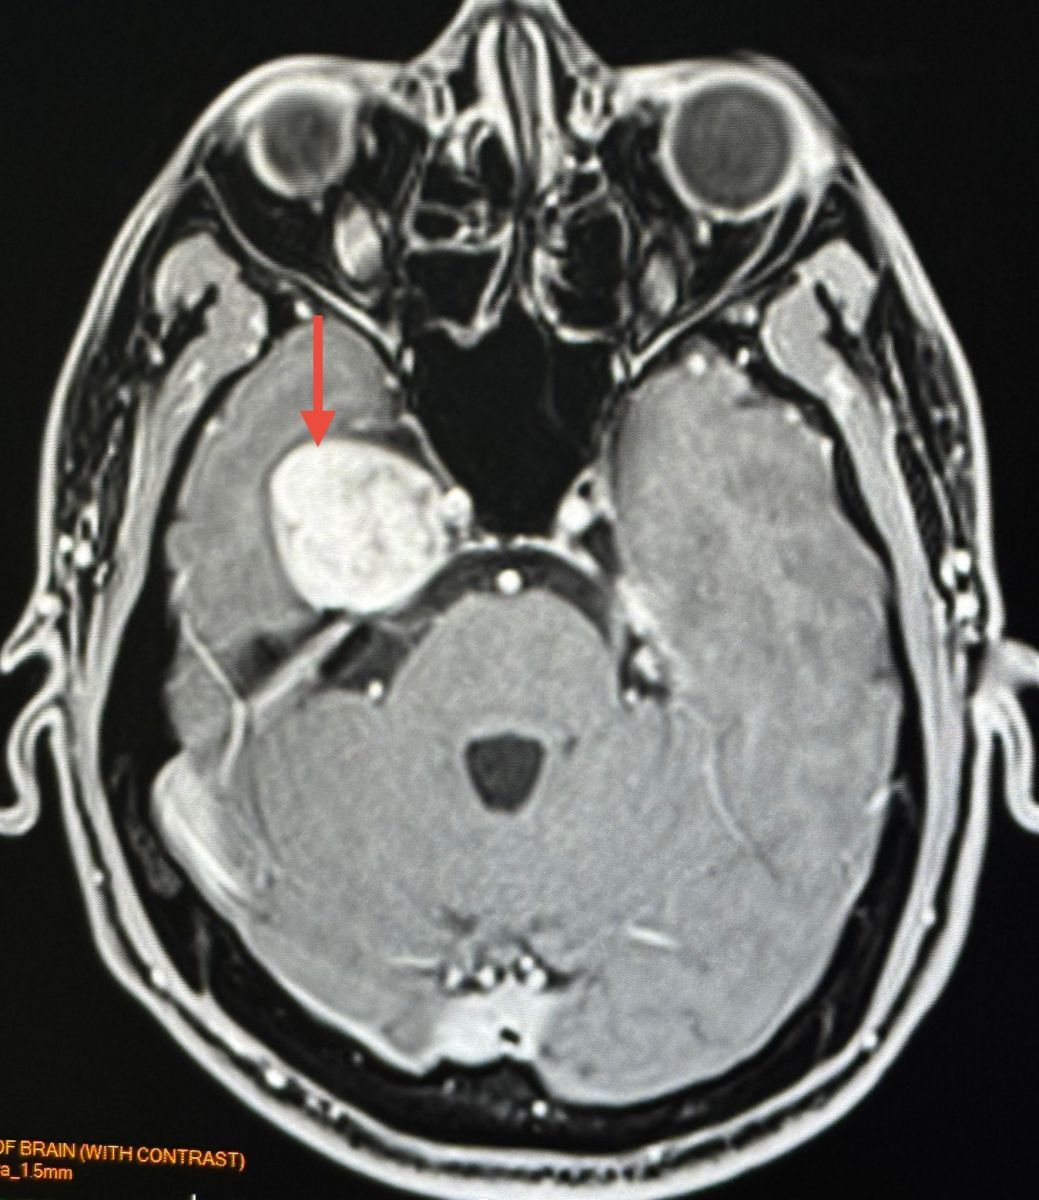

ทำคอมพิวเตอร์ CT สมองพบก้อนขนาด 2.7 × 3.0 × 2.9 เซนติเมตร ที่กลีบขมับของสมองด้านขวา right temporal lobe ทำ MRI (Magnetic Resonance Imaging) โดยใช้คลื่นแม่เหล็กไฟฟ้าและคลื่นวิทยุความถี่สูงและฉีดสี พบก้อนขนาด 3.1 × 2.9 × 2.9 เซนติเมตร สงสัย Trigeminal Schwannoma เนื้องอกของปลอกประสาทเส้นประสาทสมองเส้นที่ 5 ข้างขวา

อาการปวดศีรษะหายเอง ไม่ปวดอีกเลย ผู้ป่วยมีเนื้องอกในสมอง ตรวจเจอโดยบังเอิญจากการทำคอมพิวเตอร์สมอง

Trigeminal Schwannoma คือเนื้องอกชวานโนมาที่เกิดจากเซลล์ชวานน์ (Schwann cells) ซึ่งเป็นเซลล์ที่ทำหน้าที่สร้างเยื่อไมอีลินที่ห่อหุ้มเส้นประสาท โดยเนื้องอกชนิดนี้เกิดขึ้นบริเวณเส้นประสาทไทรเจมินอล ซึ่งเป็นเส้นประสาทสมองเส้นที่ 5 เนื้องอกชนิดนี้พบน้อยมากๆ ส่วนใหญ่เป็นเนื้องอกไม่ร้ายแรง (benign) โตช้า รักษาด้วยการผ่าตัด หรือฉายแสง